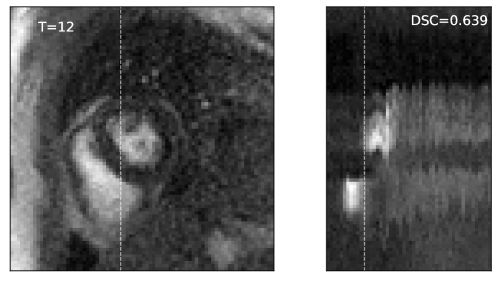

Spatiotemporal motion estimation. Motion estimation of dynamic medical images is essential in quantifying tissue properties from images acquired after the injection of some contrast agent. For instance, the cardiac perfusion sequences are used to calculate the myocardial perfusion reserve (MPR), i.e. the ratio of myocardial blood flow at stress versus rest, which provides prognostic value in assessing suspected cardiovascular disease. However, motion artefacts may hamper the accuracy and robustness of image-based quantification [38]. We therefore investigated the performance of the proposed algorithm in correcting motion artefacts for the cardiac perfusion MR images. Unlike difference in imaging modalities for multimodal groupwise registration, the appearance variation of perfusion MR comes from the contrast agent, and the number of images to be registered as well as the degree of freedom with the transformation model are much larger, requiring more robust yet efficient groupwise similarity metrics. The test images were from the MoCo dataset. Both quantitative and qualitative results were compared with alternative registration methods, including the variance of intensities (VI) [21], the congealing algorithm (CG) [3] and the conditional template entropy (CTE) [6].